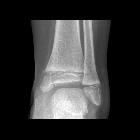

Salter-Harris type III fracture

The fracture line is often obliquely oriented through the epiphysis to the physis where it will take a horizontal orientation extending to the edge of the physis.

Salter-Harris type III fractures describe a fracture through the epiphysis extending and continuing to the edge of the physis.

- fracture through the epiphysis that is vertical/oblique in orientation

- fracture through the physis that is horizontally oriented to the periphery

- no fracture of the metaphysis

- angulation, displacement and rotation may occur